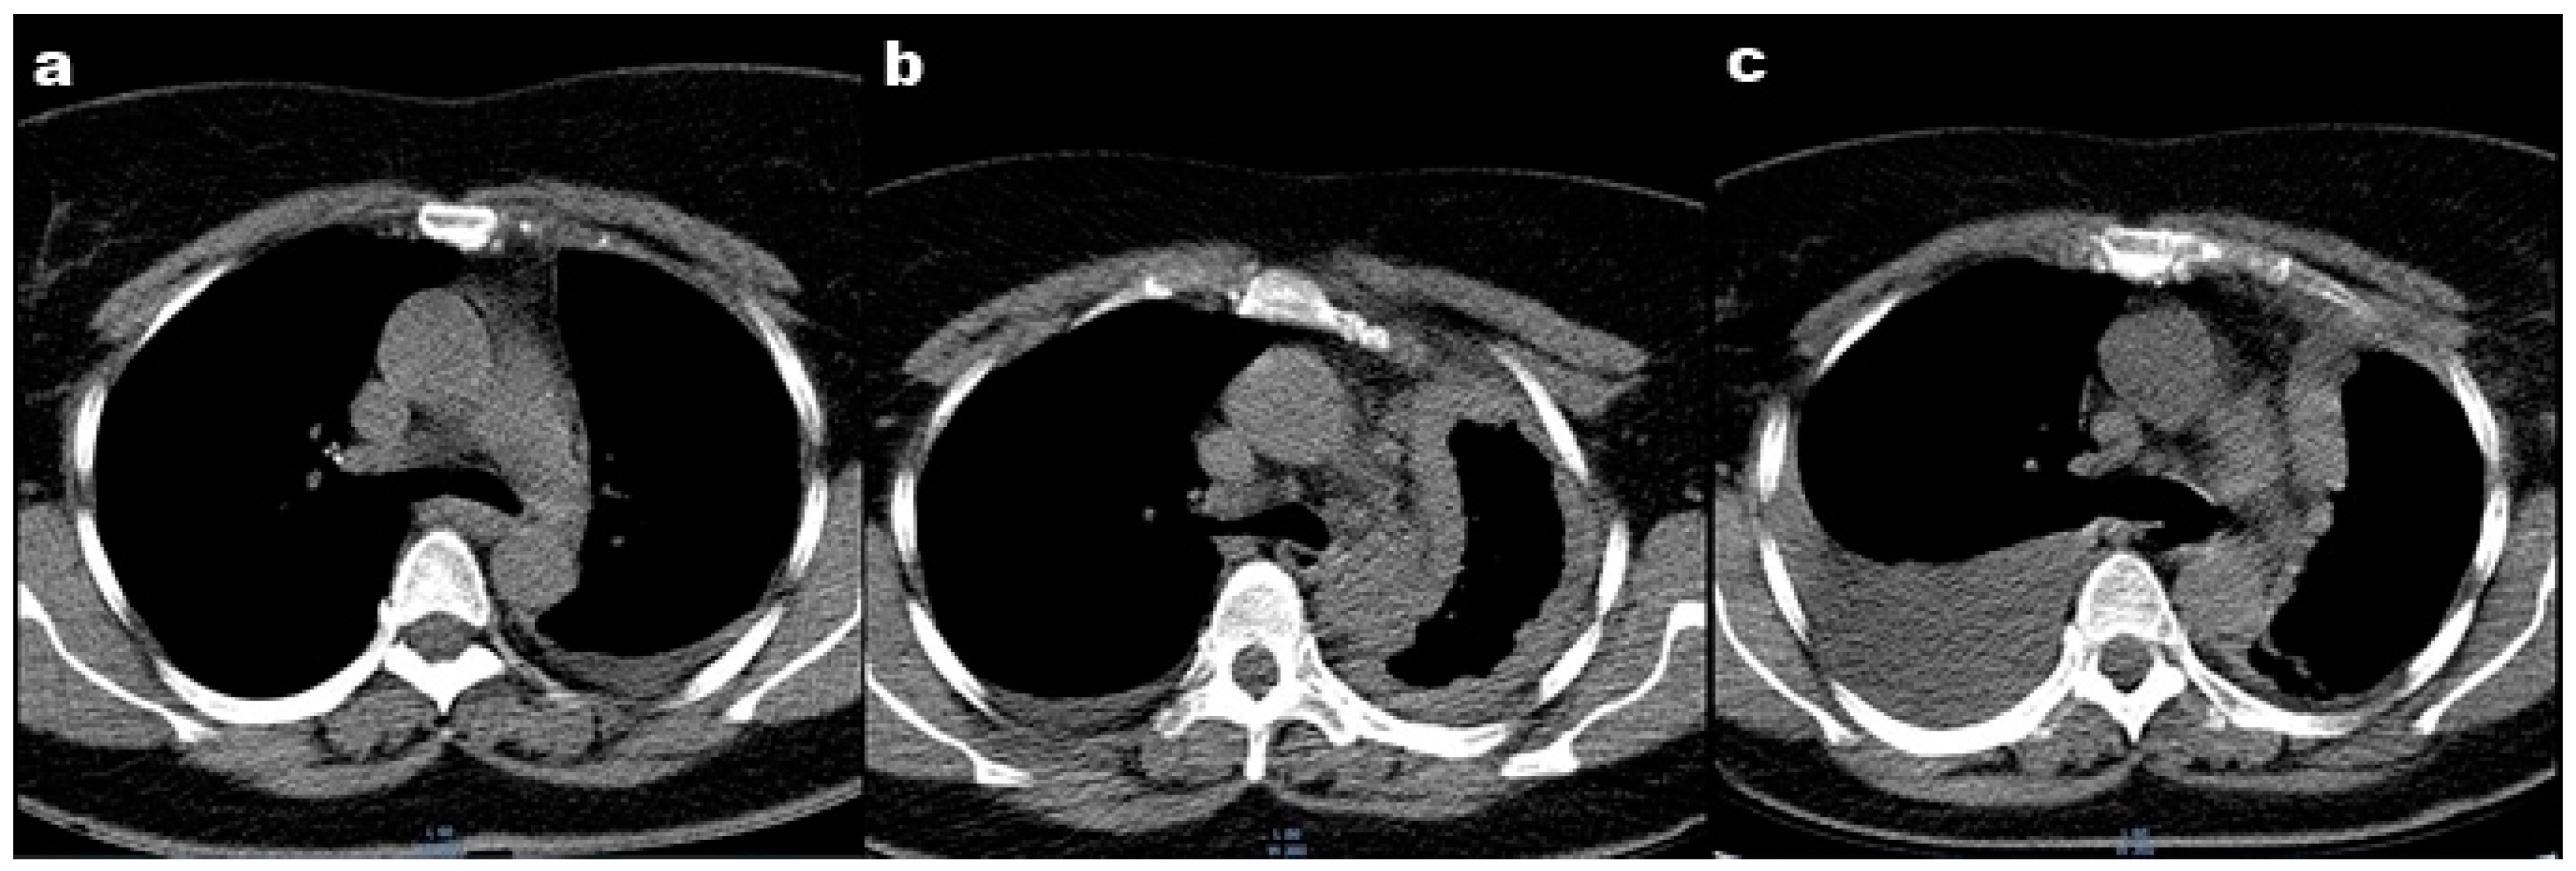

In 2019, the patient was admitted to a local hospital in the respiratory department for dyspnea on exertion during moderate physical activity. A clinical evaluation and thoracic computed tomography (CT) revealed the presence of pleural effusion in the left hemithorax (Figure 1a). The result of the biochemical and cytological analysis of the pleural fluid showed a lymphocyte-predominant exudate. The patient was diagnosed with pleurisy of an unspecified etiology, and antibiotic and anti-inflammatory treatment was recommended for 7 days. The evolution was favorable, and the pleural fluid was reabsorbed.

Figure 1.

Thoracic computed tomography: (a) Thoracic CT performed in 2019 showing pleural effusion in the left hemithorax; (b) Thoracic CT performed in 2021 showing pleural effusion in the left hemithorax; (c) Thoracic CT performed in 2022 showing right pleural effusion.

In September 2021, the patient was admitted to a thoracic surgery department. A thoracic CT showed pleural effusion (Figure 1b). Thoracentesis and a pleural biopsy were performed, and the patient was diagnosed with “Diffuse malignant mesothelioma with epithelioid elements”.

In January 2022, the patient’s condition worsened, and the patient reported dyspnea at rest and orthopnea. A thoracic CT showed right pleural effusion (Figure 1c). Thoracocentesis was performed, and the analysis of the pleural fluid revealed the presence of lymphocytes and mesothelial cells. The cultures for mycobacterium tuberculosis were negative. Following antibiotic and anti-inflammatory treatments, a slight improvement in dyspnea was noticed.